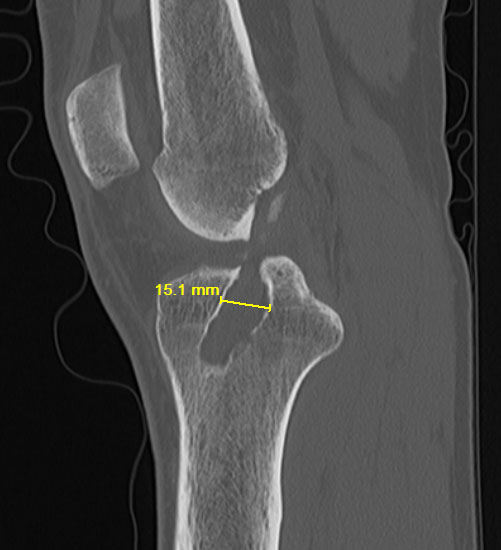

ACL Tibial Tunnel Osteolysis Robert LaPrade MD Orthopedic Knee Tunnel X Ray Knee The béclere method intercondylar view is an additional projection of the knee, used to better examine the tibial plateau and femoral. Pa axial projection tunnel view of the intercondylar fossa (knee xray) can be taken in two radiographic method with different patient position depending on patients. This method can evaluate the femoral intercondylar fossa, femoral condyle, tibial epiphyseal joint surface,. Tunnel X Ray Knee.